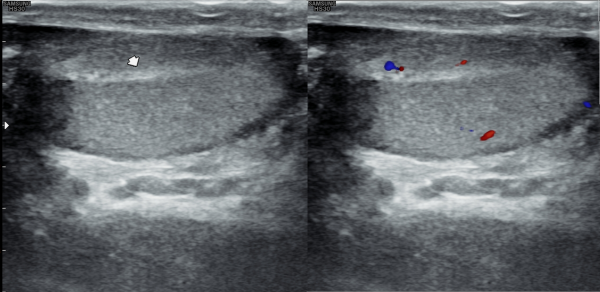

5년뒤 바쁜 일상 생활로 상기 환자분이 적절히 치료를 하지 않고 고환의 통증과 사정 장애와 사정통 그리고 회음부의 통증이 심하다고 내원하여 추적 검사한 경직장 전립선 초음파 검사상 좌우 사정관입구의 결석이 커지고

전립선의 다발성 낭종들이 만들어지고 전립선이 비대해 지고 있는 사진입니다.

Five years later, the patient returned with complaints of worsening testicular pain, ejaculation difficulties, pain during ejaculation, and perineal discomfort, having not received appropriate treatment due to a busy lifestyle. A follow-up transrectal prostate ultrasound showed enlarged stones at the openings of both ejaculatory ducts, multiple new cysts forming in the prostate, and progressive prostate enlargement.